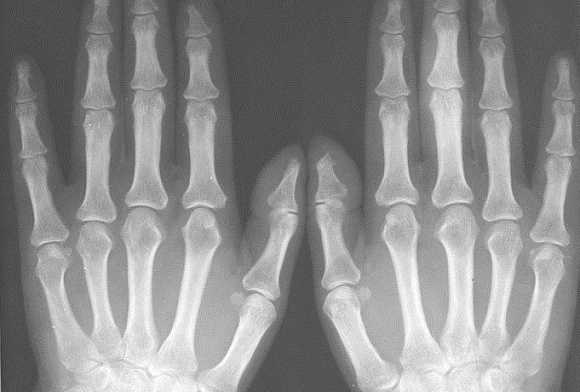

Рентген лучезапястного сустава и кисти рук: что это такое и что он показывает?

Рентген лучезапястного сустава и кисти рук - это наиболее распространённая диагностическая процедура, используемая для исследования строения, структуры, целостности костной ткани запястья и кисти рук. Её можно сделать практически в каждой государственной поликлинике или частной клинике. Рентген не требует особой подготовки - нужно просто снять с рук все кольца, часы, браслеты, наклеенный пластырь. Если на кисть ранее был наложен гипс, то, возможно, потребуется снять и его - точные рекомендации даст врач-рентгенолог.

В идеале рентгеновские снимки в нескольких проекциях должны отобразить все составляющие кости и суставы запястья и кисти: 3-гранная, полулунная, ладьевидная, гороховидная, крючковатая, головчатая, трапециевидная кости, лучезапястный сустав, пястные кости, запястно-пястные суставы, межзапястный сустав, фаланги.

При болях, нарушении функции кисти или запястья только на одной руке для определения отклонений от нормы могут сделать рентген-фото лучезапястного сустава и кистей обеих рук.

Какие изменения видны на рентгенограмме кисти?

Травматические повреждения

Травматические повреждения, такие как переломы, вывихи, трещины, смещения, - это первое, что можно обнаружить на рентгене лучезапястного сустава. Кости запястья, рентген которых показал перелом, имеют на снимке тёмные полосы различной локализации, размера и направления.

Поставить диагноз «Вывих» по рентгену можно, если на снимке видно, что суставные поверхности костей предплечья перекрещиваются или щель между костями лучезапястного сустава не видна.

Ревматические поражения

Поражения ревматического характера могут наблюдаться, например, при патологии соединительной ткани сустава (ревматоидный артрит, склеродермия) или при воспалительных заболеваниях, поражающих костную ткань кистей и запястья.

Типичными признаками артритов кистей рук являются кистозные изменения, визуализируемые на рентгене уже на ранних стадиях развития ревматоидной патологии. Обычно они имеют небольшой размер и округлую форму. Запущенные стадии артрита характеризуются формированием крупных и плотных костных эрозий.

Рентген кистей рук при ревматоидном артрите - важная диагностическая процедура, которая позволяет точно выявить стадию развития заболевания. Главными рентген-признаками данной патологии являются припухлости мягких тканей сустава. Также об артрите свидетельствует незначительное сужение межсуставной щели и визуализируемый остеопороз. На более поздних стадиях развития патологии будут видны эрозии костей, которые имеют вид некрупных краевых дефектов в суставных концах костей. В эпифизах костей фаланг пальцев могут виднеться округлые просветления.

При проведении рентгена кистей рук с функцией увеличения изображения можно выявить нарушение целостности замыкающих пластинок уже на первых стадиях развития ревматоидного артрита. По мере прогрессирования заболевания будет наблюдаться ухудшение картины - сустав будет становиться всё уже, появятся очаги эрозии, станет ярче выраженность остеопороза. В результате разрушения суставных концов кости могут появиться подвывихи.

Нормальные показатели

В норме кости кистей рук должны иметь однородную структуру. На снимках не должно быть затемнений на белых участках. Между костями должна присутствовать щель.

Если повреждению подверглась только одна кисть, для более точного диагностирования патологии могут сделать рентген и здоровой конечности. Так будет легче провести сравнение и выявить отклонения.